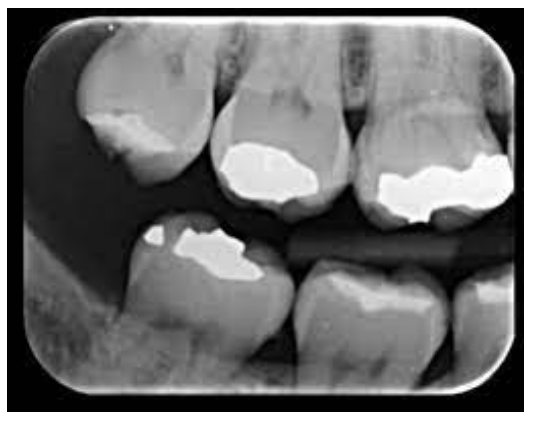

A radiografia ilustrada acima refere-se a uma: